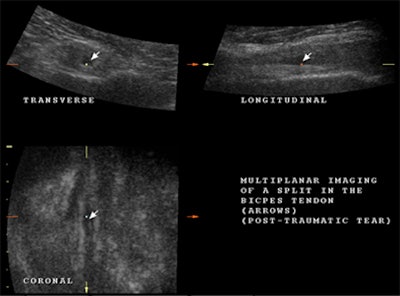

The biceps tendon may have a partial tear, either horizontally or longitudinally. Be sure that the second structure is a part of the biceps tendon and not a loose body within the tendon sheath, giving the appearance of the second tendon in cross-section.

![]() |

| A lengthways split results in two cords, giving the appearance of two tendons lying side by side over a variable length of the tendon, as may be seen in the multiplanar images above. |